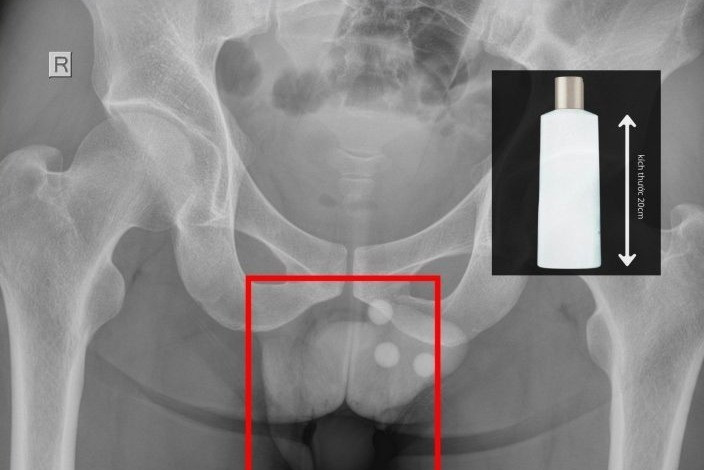

Các bác sĩ Bệnh viện Đa khoa Xuyên Á Đức Hòa đã kịp thời phẫu thuật lấy dị vật chai nhựa 20 cm kẹt sâu trong trực tràng bệnh nhân.

Vào viện với cơn đau rát dữ dội vùng hậu môn, người đàn ông được xác định có một chai nhựa dài khoảng 20cm mắc kẹt sâu trong trực tràng.

Hình ảnh X-Quang thấy chai nhựa trong trực tràng - Ảnh BVCC

BS.CKII Nguyễn Vũ An, Trưởng khoa Ngoại Tổng quát cho biết, qua thăm khám và chụp X-quang, chúng tôi xác định dị vật nằm sâu trong trực tràng, không thể lấy bằng thủ thuật thông thường. Ê-kíp đã tiến hành gây tê tủy sống, nong hậu môn và cẩn trọng lấy dị vật ra ngoài.